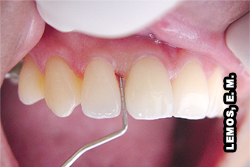

Aspecto clínico do dente 11 e 21. Com relação ao dente 11, encontra-se com a polpa sã, apenas indicou-se a pulpectomia por razões da reabilitação protética   Aspecto clínico do dente 11 e 21, o paciente não relata nenhum sinal e sintoma com relação à dor   Aspecto radiográfico do dente 11 e 21

Dente 11, pulpectomia por razões protéticas e cirurgia de acesso atípica, pela incisal, devido planejamento protético - retentor de PPF   Aspecto radiográfico do dente 11 e 21, após tratamento no 11 e retratamento endodôntico no 21 e instalação dos retentores intra-radiculares   Aspecto clínico após reabilitação protética